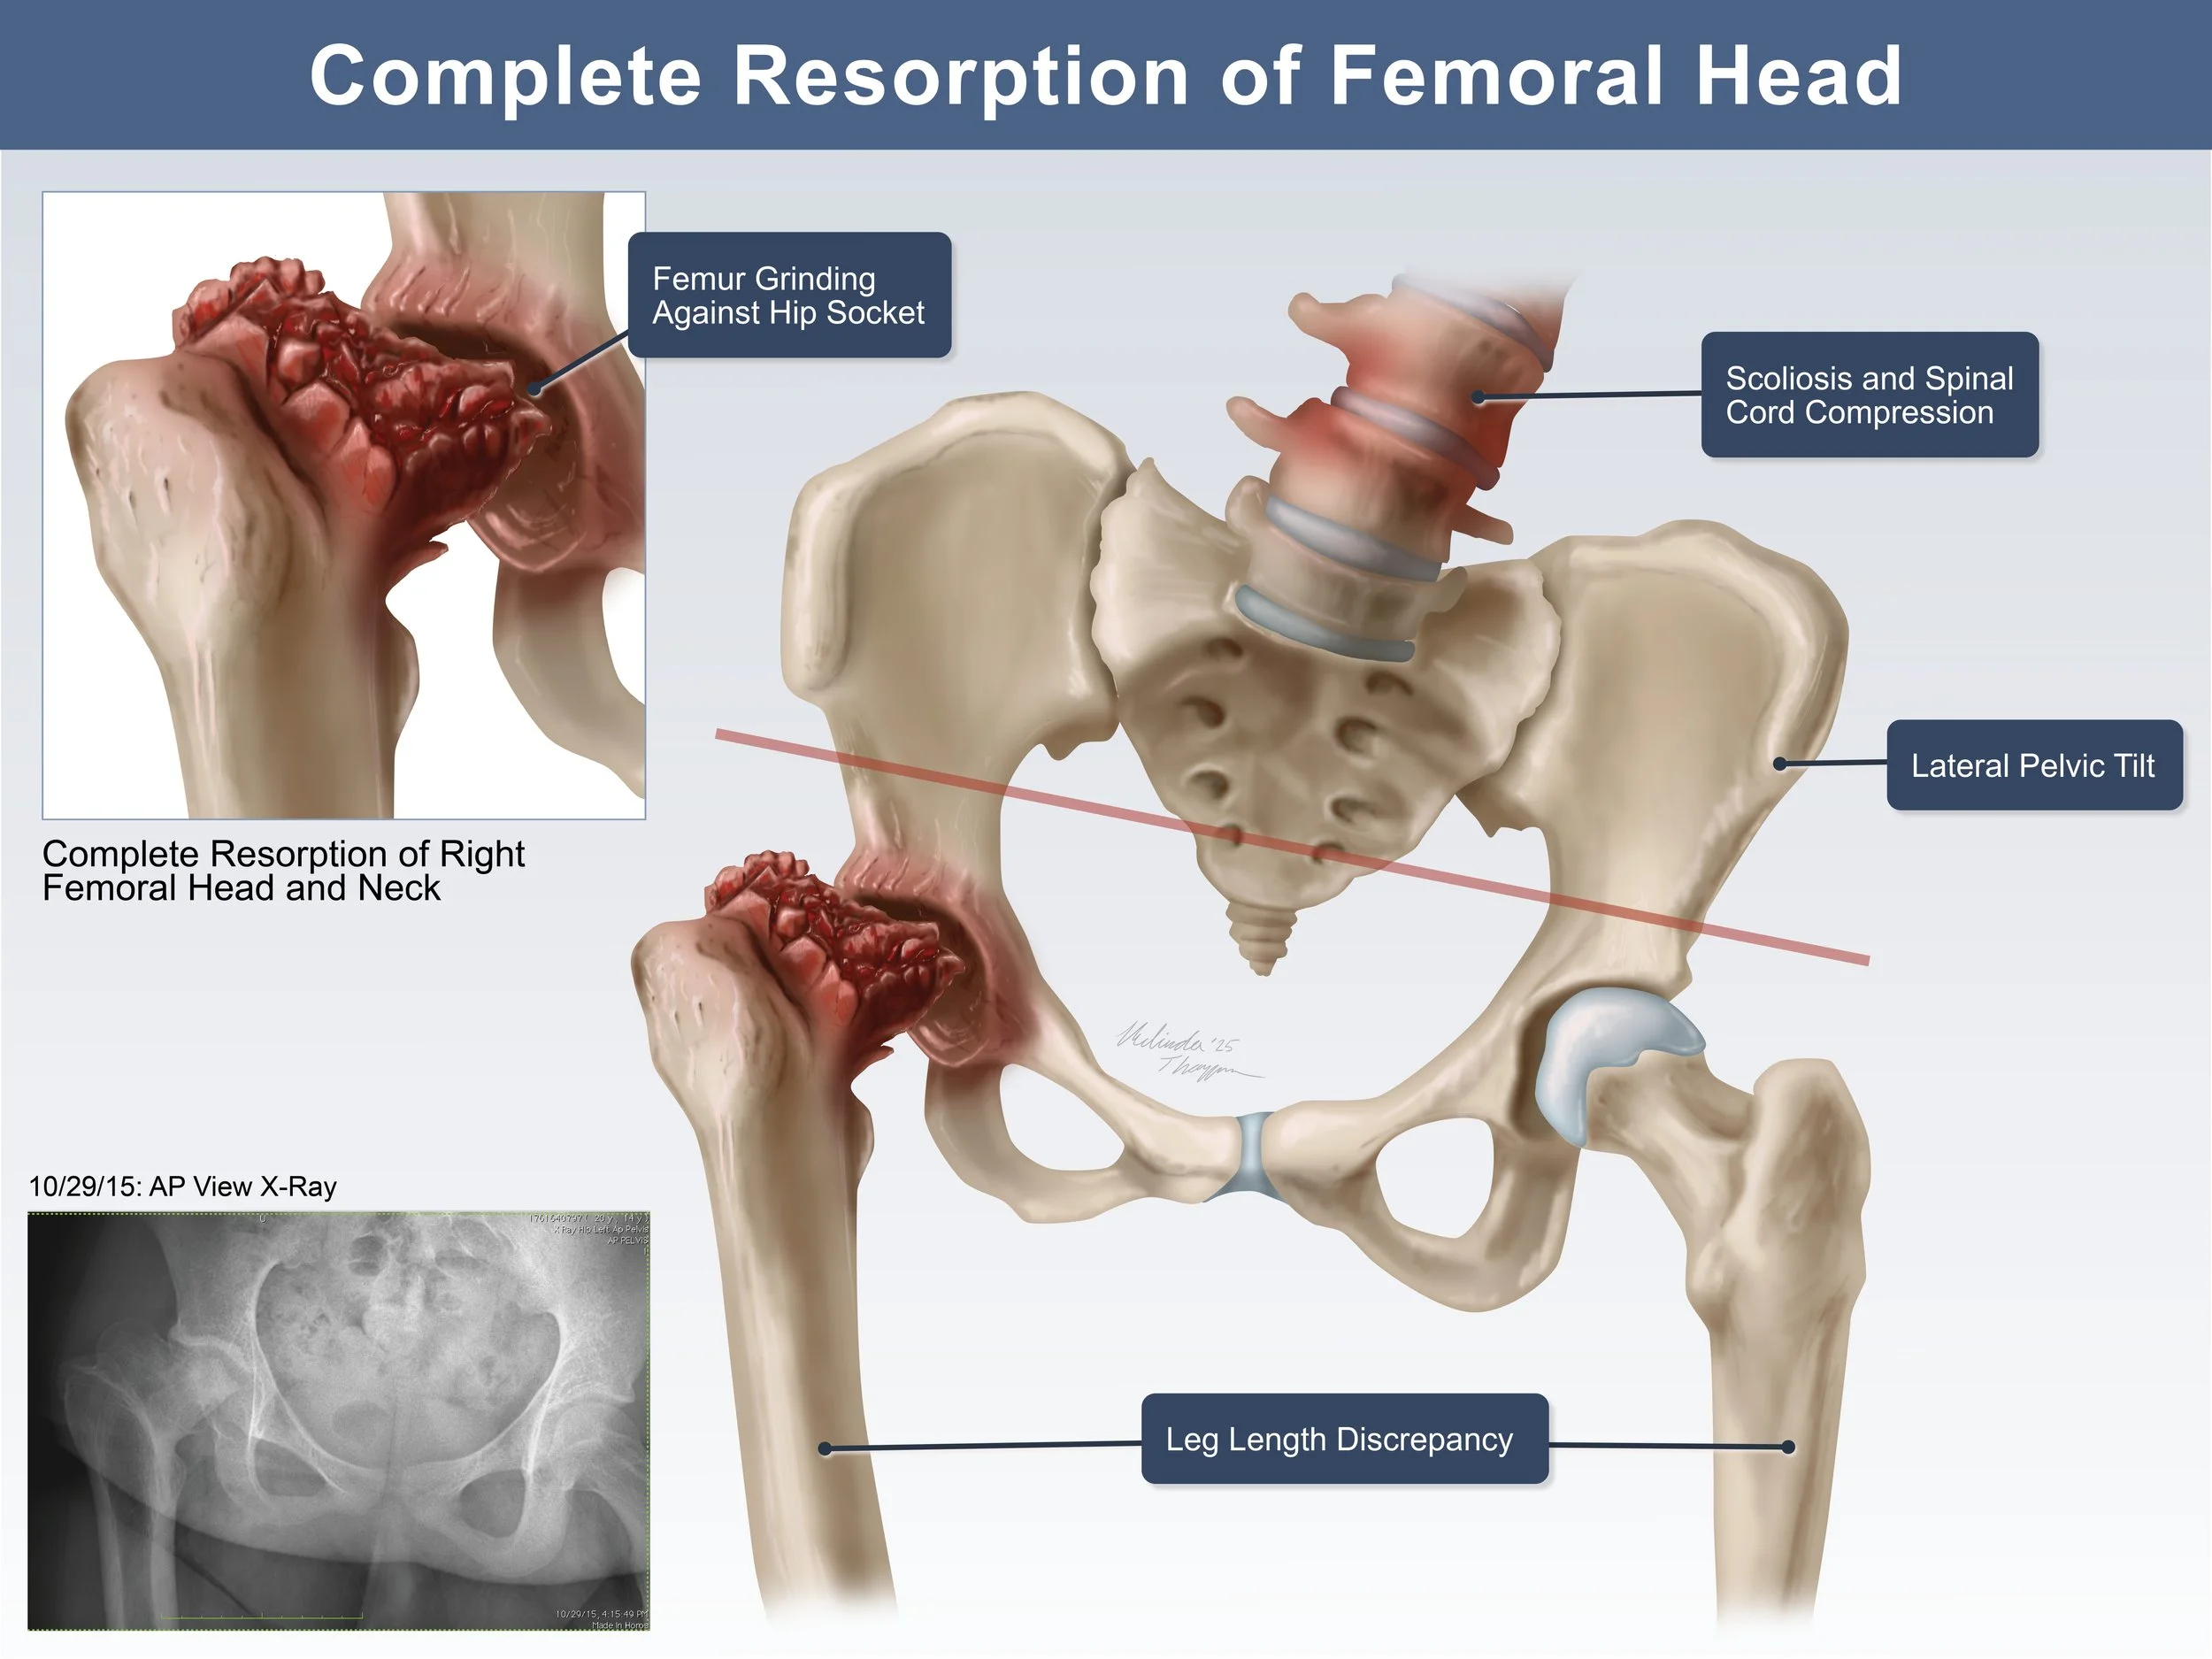

Medical Legal Illustration

Medical Illustration is important in the courtroom for many reasons including communicating scientific information for a lay audience, highlighting injury or anatomical differences, or simply representing potentially disturbing images in a more digestible way. Legal illustrations must be accurate, but still serve to help tell the defendant or plaintiff’s story.

SCFE Exhibit Design

These illustrated slides were created for a medical legal illustration course to accompany the plaintiff’s case in a “mock trial” presentation. The illustrations show the the progress of a slipped capital femoral epiphysis fracture (SCFE) that ultimately led to disability in a young girl. The illustrations were used to clearly communicate x-ray information to a lay audience and demonstrate why the doctor’s misread was easily avoidable. Additionally, the illustrations show the progression of symptoms as a result of that first missed diagnosis.

Adobe Photoshop, Indesign